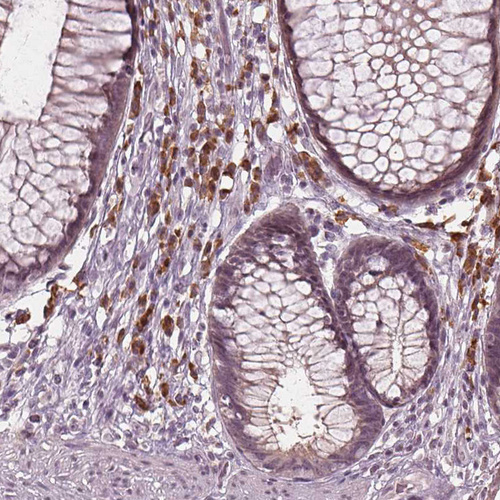

Immunohistochemical staining of human lymph node shows moderate positivity in non-germinal center cells.